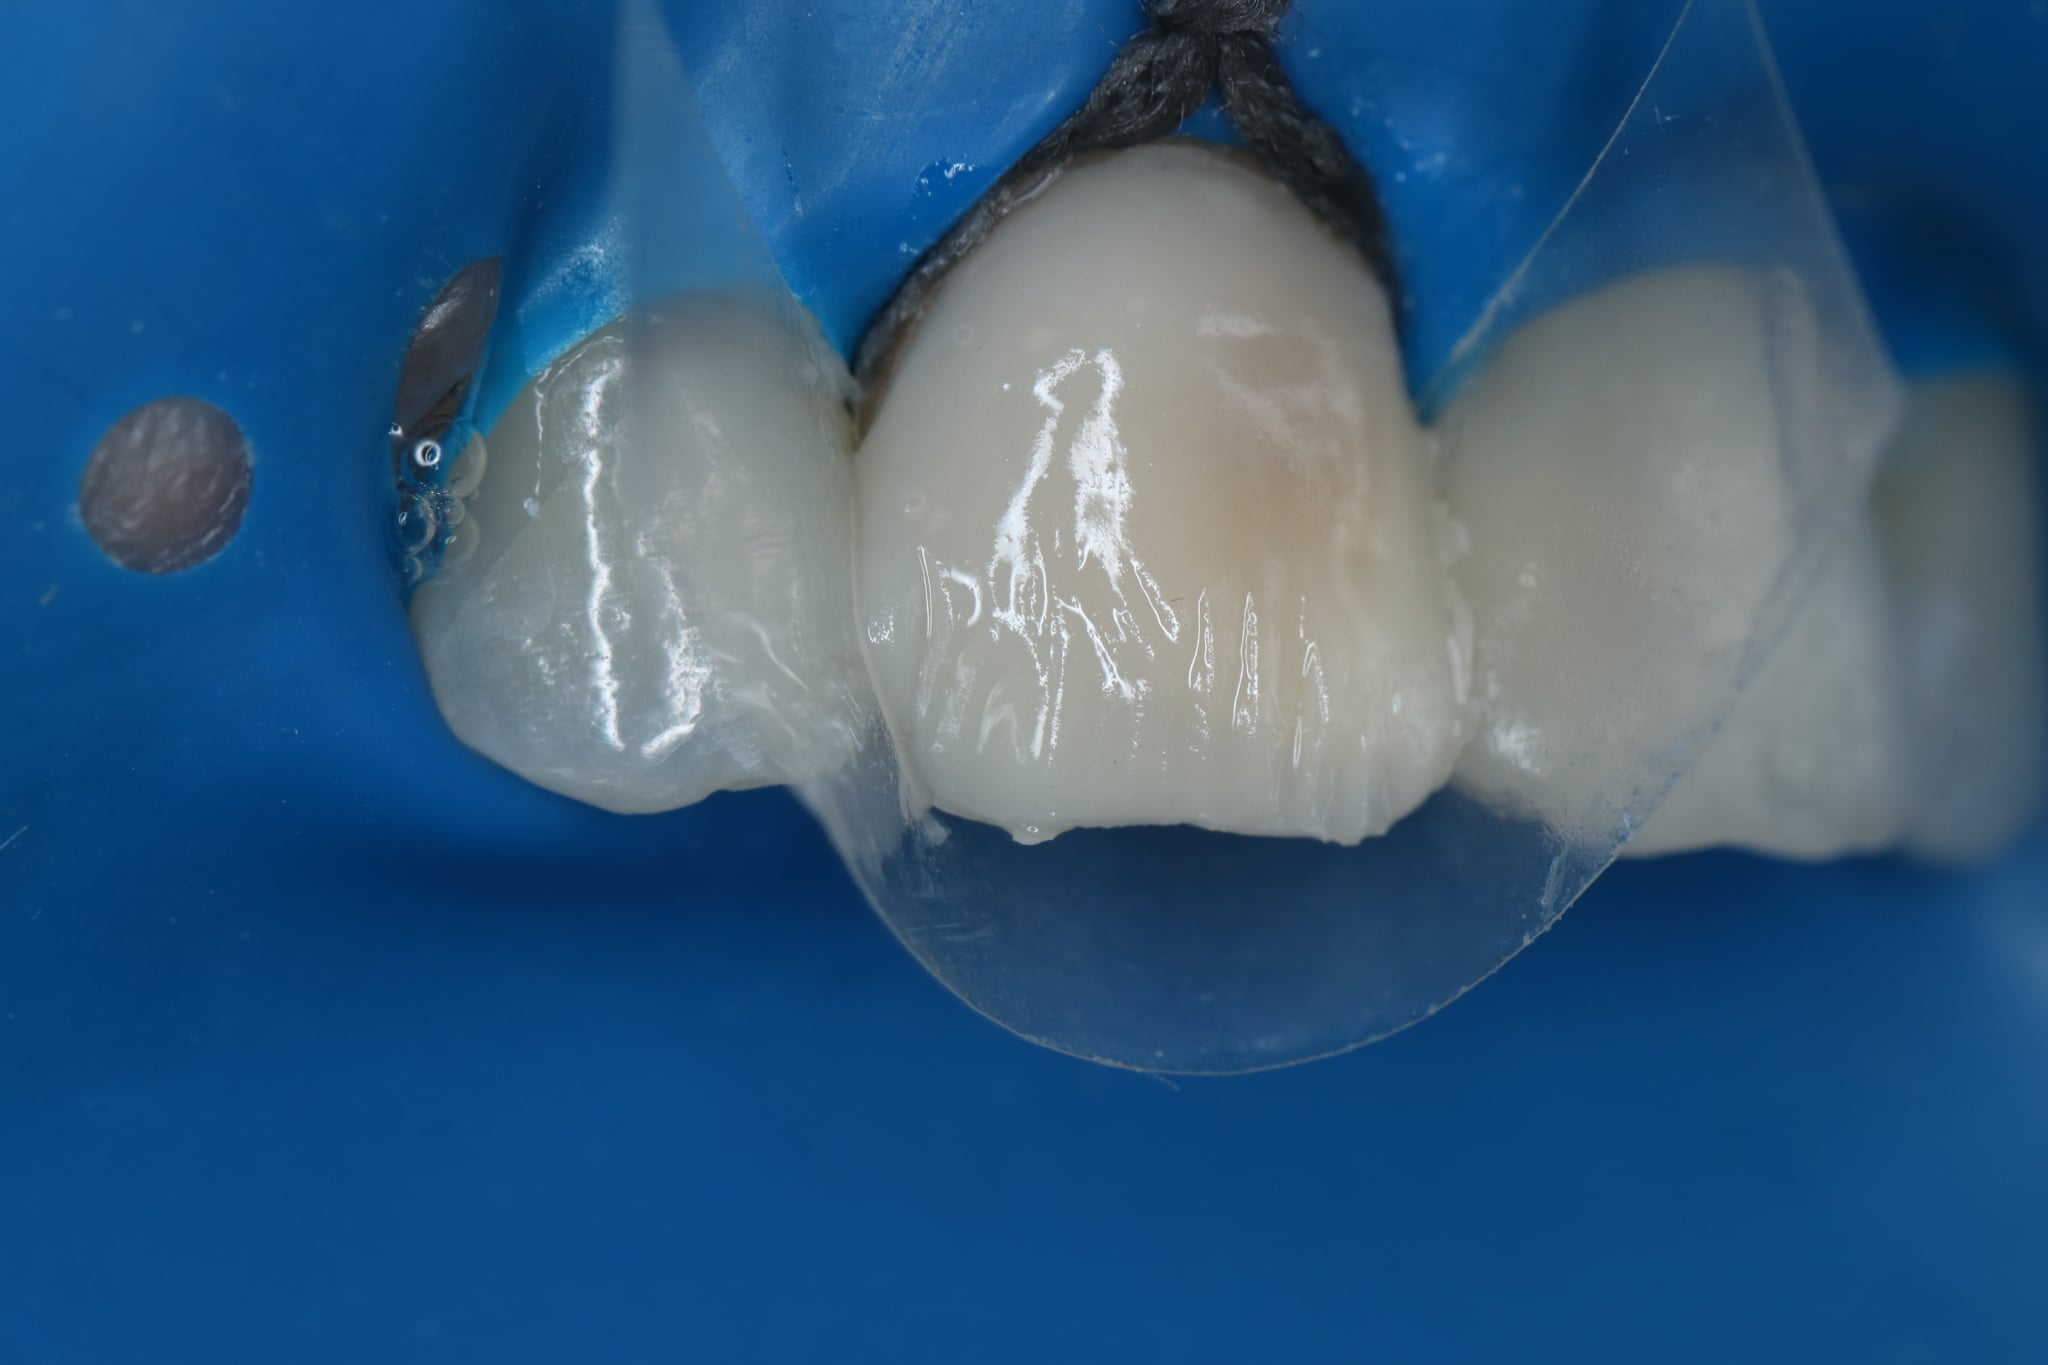

КОМПОЗИТНИ ФАСЕТИ ПРИ МЪРТВИ ПРЕОЦВЕТЕНИ ЗЪБИ

• Course

• 1 Lesson

• 30-day access

ВСЕКИ от нас ДЕНТАЛНИТЕ ЛЕКАРИ сме имали случай, в който при нас идва пациент с мъртъв преоцветен зъб и иска да се коригира естетически САМО този КОНКРЕТЕН зъб. И всички знаем колко е трудно да се постигне идентичност със съседните зъби, особено, ако са витални. Днес ще се научите всички тайни за трансформация на ВСЕКИ мъртъв преоцветен зъб в дентален шедьовър, колкото и да е трудно. Запис на LIVE WEBINAR